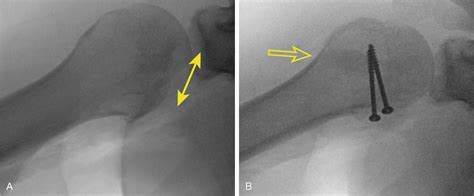

In some cases, surgical treatment may be necessary to address Hill Sachs disease, particularly if the lesion is large or causing significant symptoms. Surgical options may include:

• Arthroscopic surgery: Minimally invasive surgery using a small camera and instruments to repair the Hill Sachs lesion and stabilize the shoulder joint.

• Open surgery: Traditional open surgery to repair the Hill Sachs lesion and address any other underlying issues, such as shoulder instability.

• Bone grafting: In some cases, bone grafting may be necessary to fill in the defect caused by the Hill Sachs lesion and restore the normal contour of the humeral head.